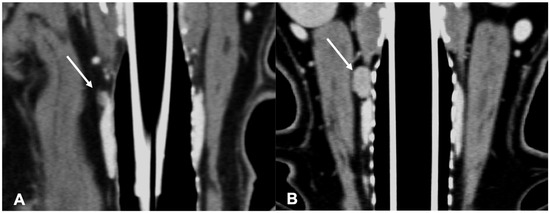

Figure 4.

CT appearance of parathyroid gland adenocarcinoma. Post-contrast dorsal CT reconstruction in two dogs with parathyroid gland adenocarcinoma (arrow) at the level of the left external parathyroid. Note the variable CT appearance: large size of the lesion in (A) showing heterogeneous contrast enhancement; the adenocarcinoma in (B) is smaller, has a rounded shape, and homogeneous contrast enhancement.